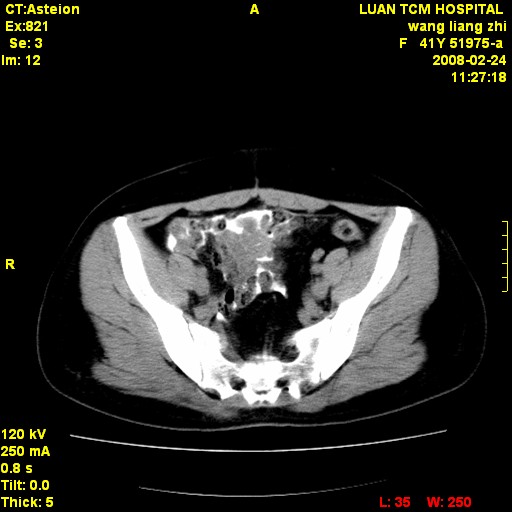

以下是引用dyqct在2009-8-23 16:17:00的发言:[br]考虑:1、造影剂进入腹腔、结肠旁沟、肝周;[br] 2、子宫明显增大(腺肌增生症?);[br] 3、膀胱显影是由于造影剂吸收后经肾分泌进入膀胱的;[br] 4、建议mri检查子宫。

以下是引用zjzjr在2009-8-23 17:28:00的发言:[br]考虑:1、造影剂进入腹腔、结肠旁沟、肝周;[br] 2、子宫明显增大(腺肌增生症?);[br] 3、膀胱显影是由于造影剂吸收后经肾分泌进入膀胱的;[br] 4、建议mri检查子宫。